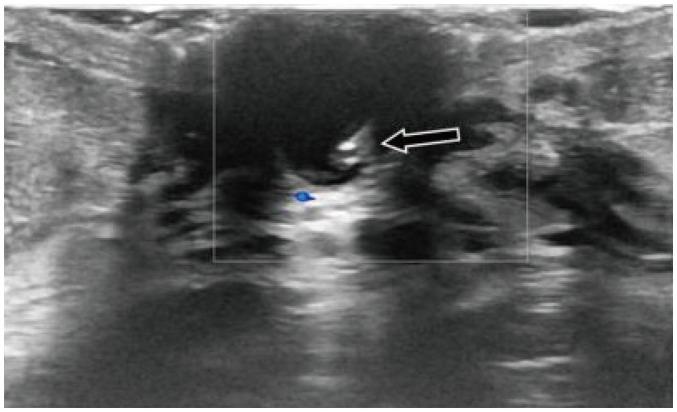

Ultrasound (US) is an attractive diagnostic approach to identify both common and uncommon nipple pathologies, such as duct ectasia, nipple abscess, nipple leiomyoma, nipple adenoma, fibroepithelial polyp, ductal carcinoma (restricted to nipple), invasive carcinoma, and Paget's disease. US is the reliable first-line imaging technique to assess nipple pathologies. It is useful to identify and characterize nipple lesions. Additionally, we have presented the mammography and MRI outcomes correlated with histopathologic features for the relevant cases.